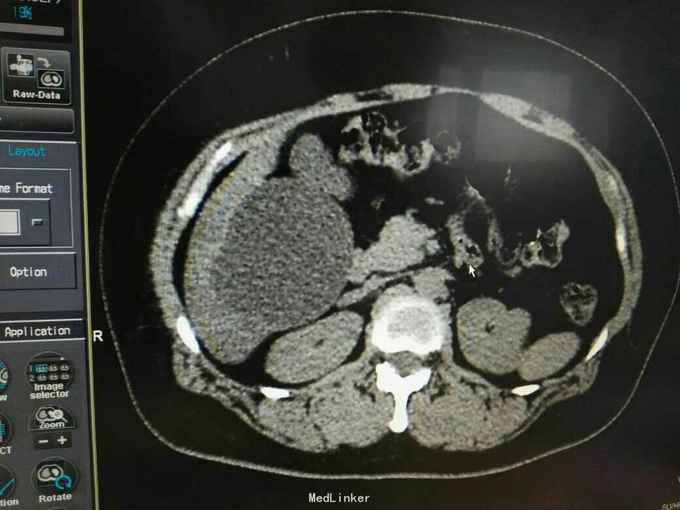

巨大肝囊肿

发现肝脏占位10年

肋弓下可触及囊性占位

肝囊肿

今日在局麻下行囊肿穿刺抽吸+无水酒精注射术 术中共抽取淡黄色液250ml